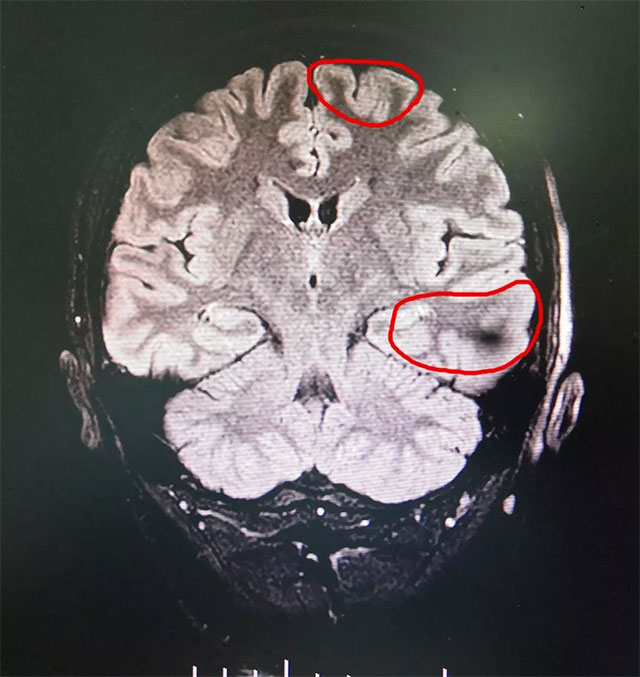

▲ 綜合MR、24小時(shí)視頻腦電等多種檢查,最終確定患者癲癇病灶

經(jīng)過(guò)檢查,患者經(jīng)系統(tǒng)內(nèi)科藥物治療不佳,確診為難治性癲癇。MRS示雙側(cè)海馬結(jié)構(gòu)異常,PET-CT顯示左側(cè)大腦代謝下降,VEEG檢查可見(jiàn)異常波:左側(cè)大腦明顯異常,大量癲癇波,結(jié)合患者病史并綜合相關(guān)檢查最終確定癲癇病灶位于左側(cè)大腦(額顳海馬)。